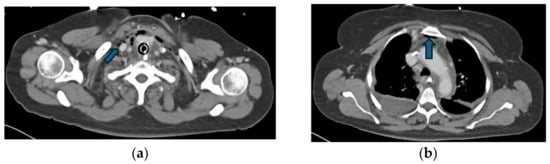

Regarding the source of infection, 77% (n = 17) of patients had DNM originating from oropharyngeal infections, while 23% (n = 5) had odontogenic sources. All patients underwent CT scans for the primary diagnosis (Figure 2 and Figure 3), and if required, serial CTs were performed to monitor the disease’s progression.

Figure 2. Hypodense formation (blue arrow) with peripheral contrast enhancement in the right retropharyngeal region, beginning paramedian caudal to the right pharyngeal tonsil/at the level of the C2 vertebral body, with gas inclusion in a patient with retrotonsillar abscess.

Figure 3. CT findings of the same patient presented in Figure 2, demonstrating the progression of DNM. (a) Gas inclusions (blue arrow) extending along the platysma muscle and thyroid gland into the anterior mediastinum; (b) Gas inclusions (blue arrow) posterior to the manubrium sterni with right sided pleural effusion.